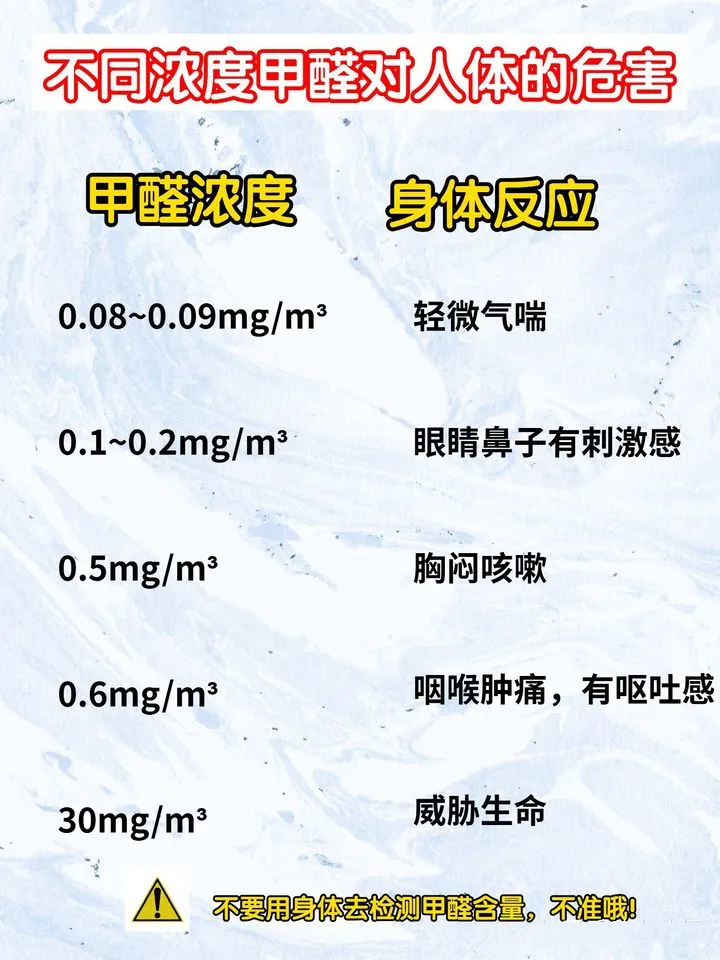

近些年來,雖然新聞媒體一再的報道甲醛中毒的事件,以提醒大家注意新裝修后場所的甲醛超標問題,但是依舊會有很多人還是會出現甲醛中毒的情況。因為他們也不清除自己到底有沒有受到甲醛的危害。入住后要記得觀察一下

長時間接觸高濃度的甲醛,很有可能會致癌2022-09-23

很多人只知道國際癌癥研究機構把甲醛列為致癌物質,但有一句非常重要的前提條件被忽略了: 職業性的甲醛接觸(在石油工業、制鞋廠、化工廠等工作的人,需要長時間接觸高濃度甲醛),與多種腫瘤的發生有關。也就

甲醛帶來的危害是在潛移默化中形成2022-09-15

會隨著在甲醛房停留時間的推移,而增加患病概率嗎? 其實“甲醛病”跟具體的時間沒有明確的關系,主要是跟室內甲醛的濃度有關系! 其中,老人、孕婦、兒童等免疫力低的人群,更容易受影響。